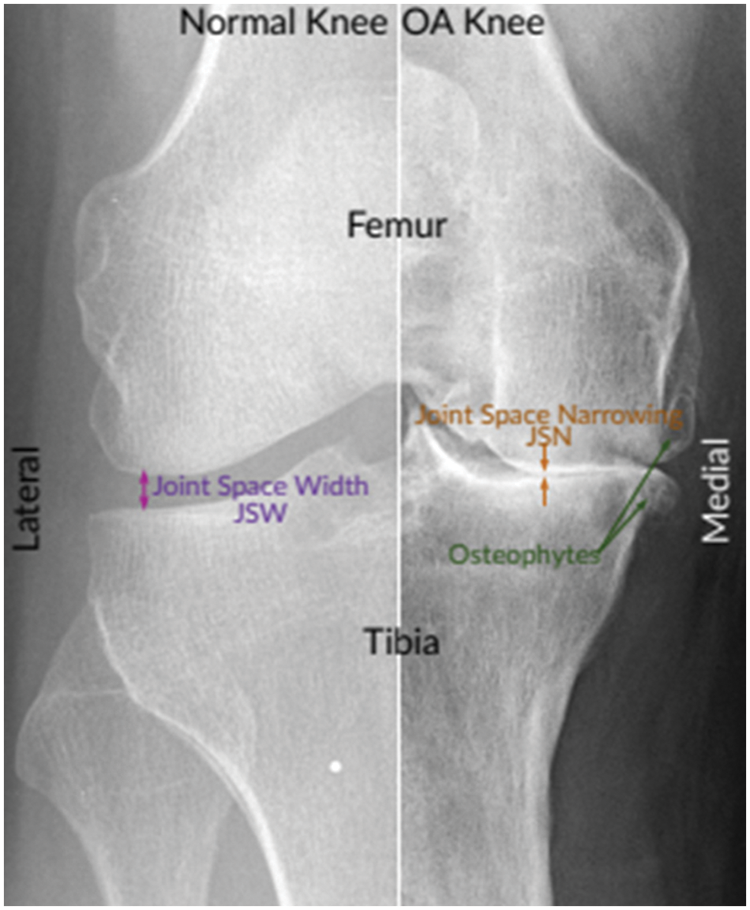

Interrogating the radiographs such as X-Ray images is a common method to diagnose the disease [5]. Radiographs (X-rays) remain the gold standard for KOA screening due to their expense, protection, wide availability, and timeliness. According to radiologists, joint space narrowing (JSN) and osteophyte development, as seen in Fig. 1, are the most conspicuous pathological characteristics of KOA. Using the Kellgren-Lawrence (KL) grading system, these two characteristics can also be utilized to assess the severity of KOA [6]. Using this method, KOA severity is graded into five categories, ranging from grade 0 to grade 4, based on the agreed ground truth categorization [7].

Figure 1: Normal and severe osteoarthritic knee [8]